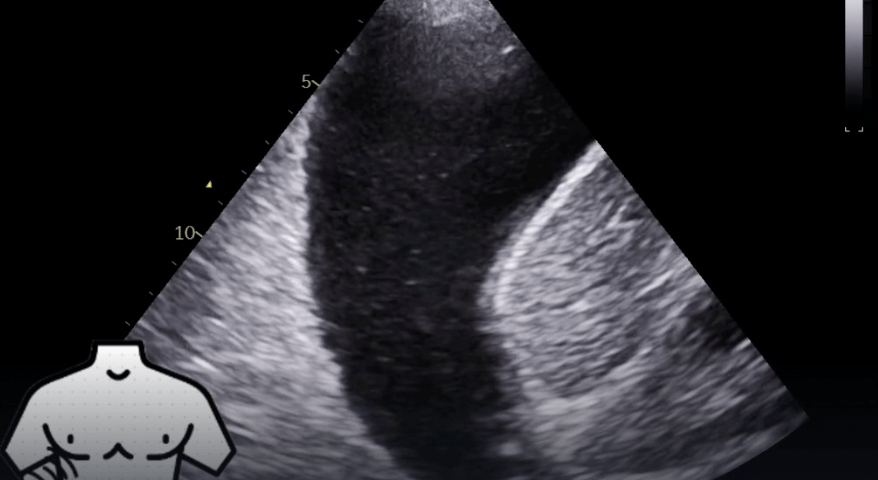

Student Image Challenge 109